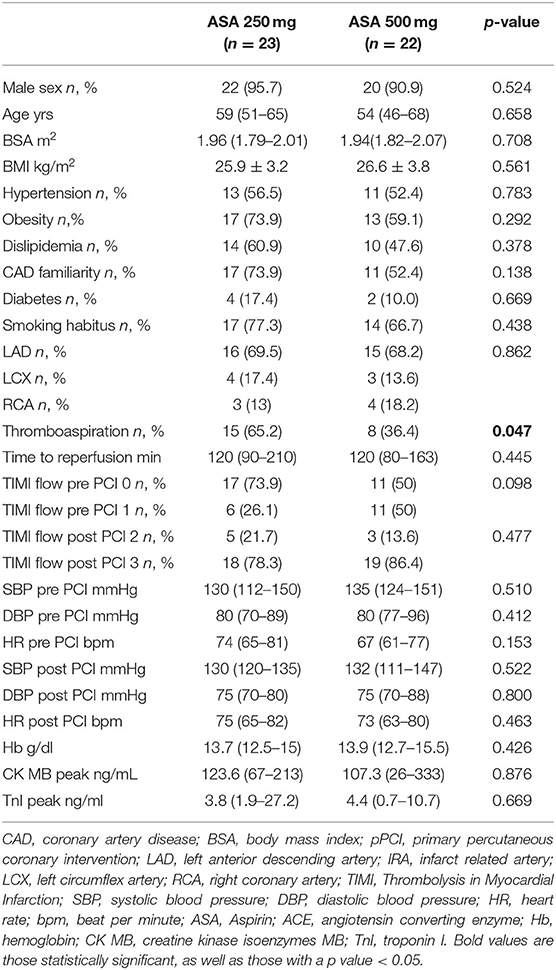

Among cardiovascular drugs administered before PCI, patients with LV adverse remodeling were less frequently treated with ASA loading dose (500 mg), compared to those with reverse or null remodeling (Table 1). Thus, we decided to assess the ASA loading dose effect according to LV remodeling groups. Among the 45 STEMI patients who received a traceable dose of ASA before PCI, 22 STEMI underwent to ASA loading dose, and 23 patients to ASA 250 mg. No differences according to demographic and clinical variables between the two groups were found (Table 3). Patients receiving ASA loading dose before PCI had lower MVO and lower IS extent at baseline and FU-CMR and better strain values (GRS and GCS) compared to those treated with ASA 250 mg (Table 4). Moreover, in the ASA loading group a significant improvement of GCS and GLS, but not GRS values, between baseline and FU-CMR exams (GCS −15.09 ± 3.8 to −16.7 ± 3.2%, p = 0.010, GLS −14.1 ± 3.9 to −15.7 ± 3.2%, p = 0.011, GRS 31.0 ± 7.8 to 32.9 ± 7%, p = 0.104) was noted. Meanwhile, no significant differences of GCS and GLS values between two paired CMR exams within the group treated with lower ASA doses (GCS −13.8 ± 3.5 to −14.1 ± 3.9% p = 0.612, GLS −12.9 ± 3.3 to −13.8 ± 3.7%, p = 0.232, GRS 28.2 ± 6.6 to 27.4 ± 7.9%, p = 0.594) were observed (Figure 4).

Table 3. Demographic, clinical, pharmacological, and angiographic characteristics according to the ASA group.